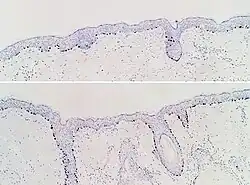

SOX10 immunohistochemistry of normal skin (top) and atypical melanocytic proliferation (bottom), seen mainly in hair follicles.

SOX10 immunohistochemistry of normal skin (top) and atypical melanocytic proliferation (bottom), seen mainly in hair follicles. -